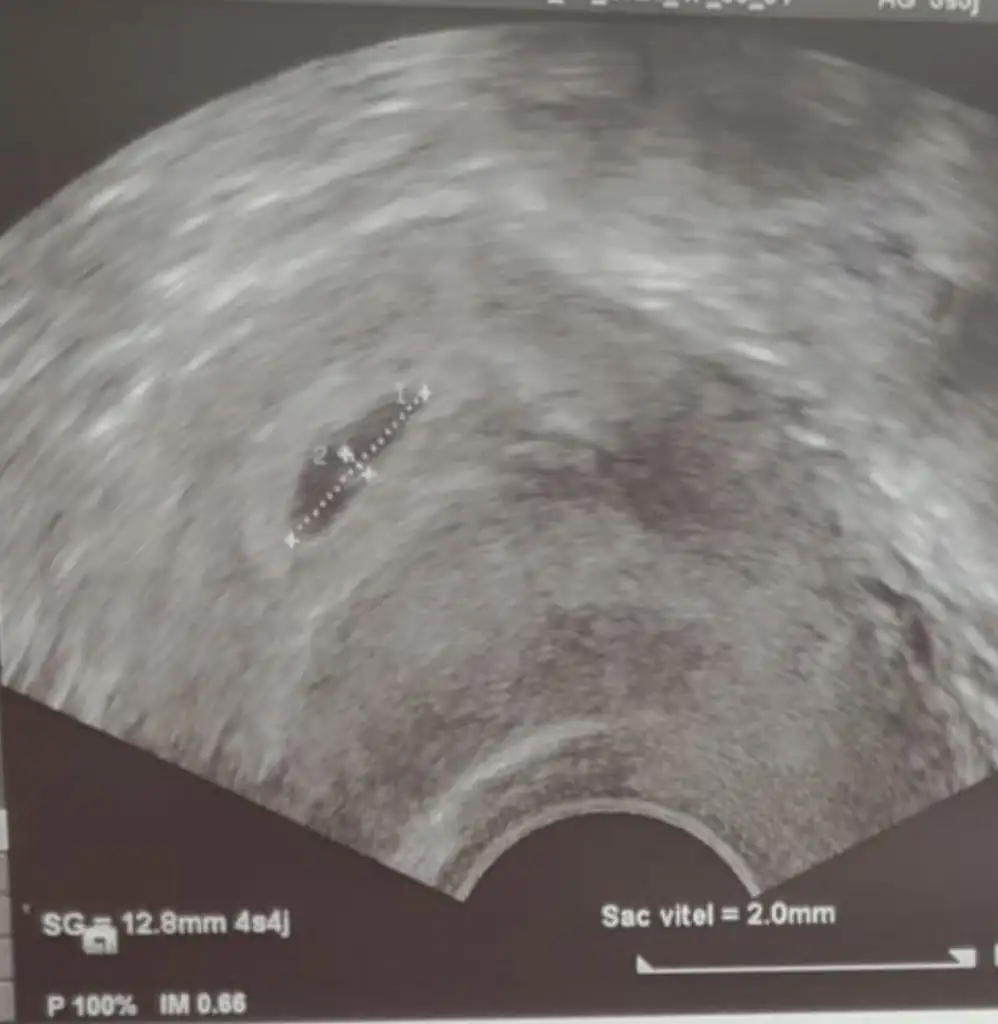

Yamuk derken neyi kastediyorlar bilmiyorum ama benim Kesem de bu sekilde yamuk gozukuyordu. Size ultrason goruntusu verdiler mi? Onun ustunde kese boyutu vs. Yazar

Kese eger o kucuk siyah nokta seklinde olan seyse baya kucuk daha. Belki de gec dollenme.. Size kese kac mm, icinde yolk sac var mi yok mu